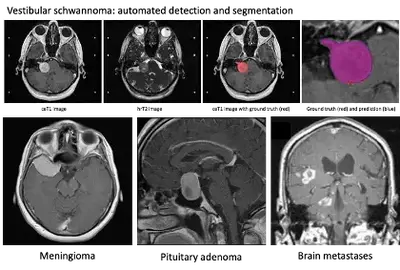

We have previously developed a fully-automated AI framework to segment a vestibular schwannoma (a type of brain tumour) from MRI achieving state-of-the-art results. This project aims to develop deep learning models to: 1) detect and automatically segment various non-glial brain tumours (meningioma, pituitary adenoma, brain metastases) using MRI; and 2) develop compositive clinical and imaging biomarkers to predict tumour growth and behaviour (pituitary adenoma, meningioma).